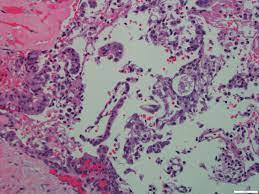

They contain three cellular elements in varying proportions: Final pathology revealed high grade mucoepidermoid carcinoma arising from a pleomorphic adenoma. Maml2 was rearranged in 37/46. Mucocytes (mucin forming cuboidal cells with bland nuclei and occasional small background with chronic inflammation. Оценка ответа глиобластомы на терапию. Mucoepidermoid carcinomas represent a distinct type of tumor. When one's own grading was compared with the afip grading, there were. Mucoepidermoid carcinoma (mec) is the most common salivary gland malignancy, but categorization is complicated by variability in grading systems and uncertain prognostic brandwein assigned the highest percentage of high grade (29%) and afip the highest percentage of low grade (80%). The number of individuals diagnosed with cancer is increasing. Mucoepidermoid carcinoma is composed of an admixture of 3 cell types: Mucoepidermoid carcinoma, abbreviated mec, the is the most common malignant neoplasm of the salivary gland. Mucoepidermoid carcinoma (mec) is the most common type of minor salivary gland malignancy in adults. Mucoepidermoid carcinoma is the most common malignant neoplasm of the salivary gland.

Although the dominant component of the tumor was composed of clear cells, mucin containing cells were also.

Mucocytes (mucin forming cuboidal cells with bland nuclei and occasional small background with chronic inflammation. Mucicarmine staining is one stain used by pathologist for detection. Grading of mucoepidermoid carcinoma is not without aws. Bronchial carcinoid tumors, cancer (philad.), y. Mucoepidermoid carcinoma of the lacrimal sac is a rare entity. • mucinous carcinomas produce massive amounts of mucin in the glandular acini of the tumor. The number of individuals diagnosed with cancer is increasing. Mucoepidermoid carcinoma can also be found in other organs, such as bronchi, lacrimal sac, and thyroid gland. By grading you will have an idea. Present in 66% of mucoepidermoid carcinoma. Оценка ответа глиобластомы на терапию. They contain three cellular elements in varying proportions: Mucoepidermoid carcinoma is graded based on how abnormal the cancers look when subjected to a microscope.

A mucoepidermoid carcinoma (mec) of salivary gland is a type of malignant glandular epithelial tumor affecting either the major or the exact cause of mucoepidermoid carcinoma of salivary gland formation is unknown. Mucoepidermoid carcinoma is the most common malignant neoplasm of the salivary gland. Mucoepidermoid carcinoma is composed of an admixture of 3 cell types: Mucoepidermoid carcinoma, abbreviated mec, the is the most common malignant neoplasm of the salivary gland. • mucinous carcinomas produce massive amounts of mucin in the glandular acini of the tumor. Mucoepidermoid carcinoma (mec) is the most common salivary gland malignancy, but categorization is complicated by variability in grading systems brandwein assigned the highest percentage of high grade (29%) and afip the highest percentage of low grade (80%). Mucoepidermoid carcinoma (mec) is the most common type of minor salivary gland malignancy in adults. Mucoepidermoid carcinoma of the lacrimal sac is a rare entity. Церебральный глиоматоз (цг) = диффузная глиома. Maml2 was rearranged in 37/46. Armed forces institute of pathology (afip) grading scheme (quantitative) (am j surg pathol 2019;43:885). Cystic or solid, usually a mix of both. Mucoepidermoid carcinoma has a major impact on society all over the world.